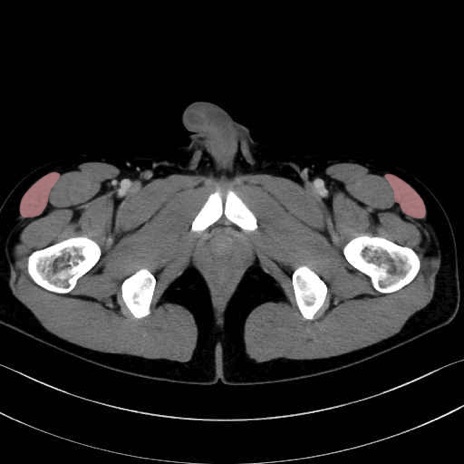

大腿筋膜張筋 (Tensor fasciae latae)